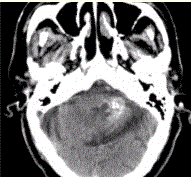

问题 男性,80岁,左耳听力下降伴头晕半年。头CT显示如下图。 关于海绵状血管瘤的描述,错误的是

选项 A.囊性血管性错构瘤,病变内反复出血,无正常神经组织 B.CNS任何位置均可发生,脑实质常见 C.病变内不同时期的出血,大小不一 D.T1WI(典型)爆米花样高信号,病变周边低信号环(含铁血黄素沉积) E.病变明显强化 F.DSA可见血管染色 G.海绵状血管瘤可多发,还可伴有发育性静脉畸形

答案 DEF